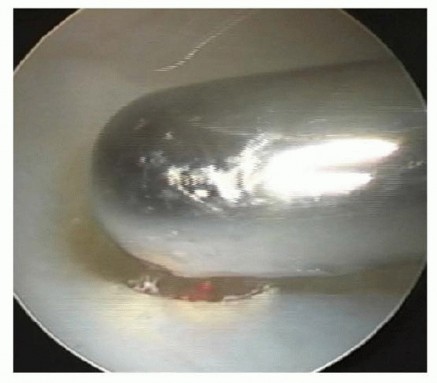

With the TFCC débrided and the ulnar head exposed, we proceed to the arthroscopic wafer procedure. This is the most technically demanding portion of the operation. The objective is to resect 2 to 3 mm of the distal ulnar dome, decorticating the articular cartilage and the underlying subchondral bone, to achieve an ulnar-minus variance.

Introduction of a high-speed, 2.9mm shielded arthroscopic burr through the central TFCC defect, making initial contact with the articular cartilage of the ulnar head.

We introduce a shielded, high-speed arthroscopic burr (typically 2.9mm or 3.5mm) through the working portal. The shield of the burr must always be oriented dorsally or towards the carpus to protect the lunate and triquetrum from catastrophic iatrogenic damage.

Active burring of the ulnar dome. The resection begins centrally and progresses radially and ulnarly. Copious irrigation is critical to clear bone debris and prevent thermal necrosis.

The resection must be systematic. I typically begin centrally and work radially towards the sigmoid notch, and then ulnarly towards the styloid. Crucially, the resection must stop short of the DRUJ. We must preserve the vertical articular surface of the ulnar head that articulates with the sigmoid notch of the radius to maintain DRUJ stability and kinematics.